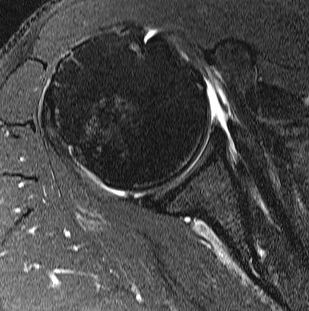

Comma Sign

Comma sign

- medially retracted subscapularis tear

- exposes the superior insertion of superior glenohumeral ligament / coracohumeral ligament

Full thickness retracted subscapularis tear with comma sign

Full thickness completely retracted subscapularis, loss of rotator interval and comma sign

Full thickness completely retracted subscapularis, loss of rotator interval and comma sign